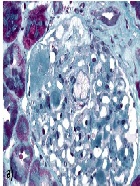

Laparoscopic Bilateral Nephrectomy Followed by Live-Related Kidney Transplant for the Treatment of Persistent Severe Nephrotic Syndrome and Advanced Chronic Renal Failure: A Case Report and Review of the Literature

Hosameldin Madkour1*, Mohamed El-Shahawy1, Rod Mateo2, Michael Koss3